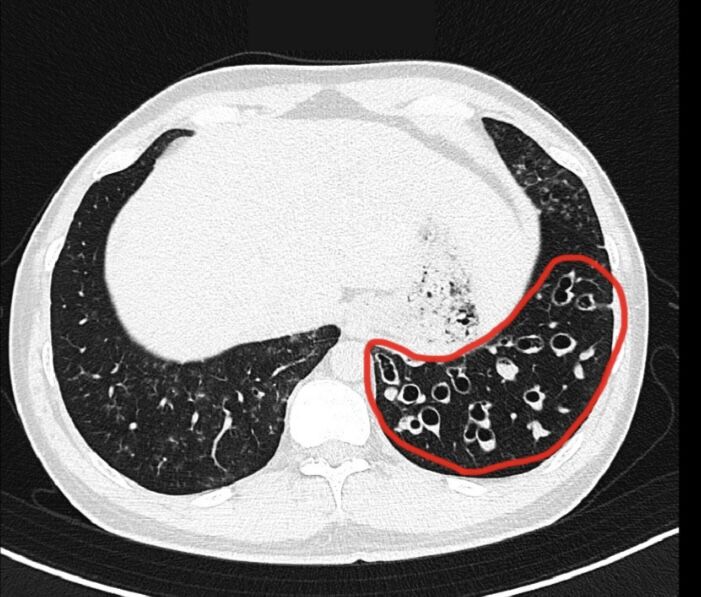

如果能夠持之以恆,早晚各做一次「肺復原氣道清潔」,約3到6個月,就能從電腦斷層的影像中,清楚看到已經擴張的支氣管內痰液,顯著減少。同時相關的症狀,像是濃痰、喘、胸悶,也能有明確的症狀改善。